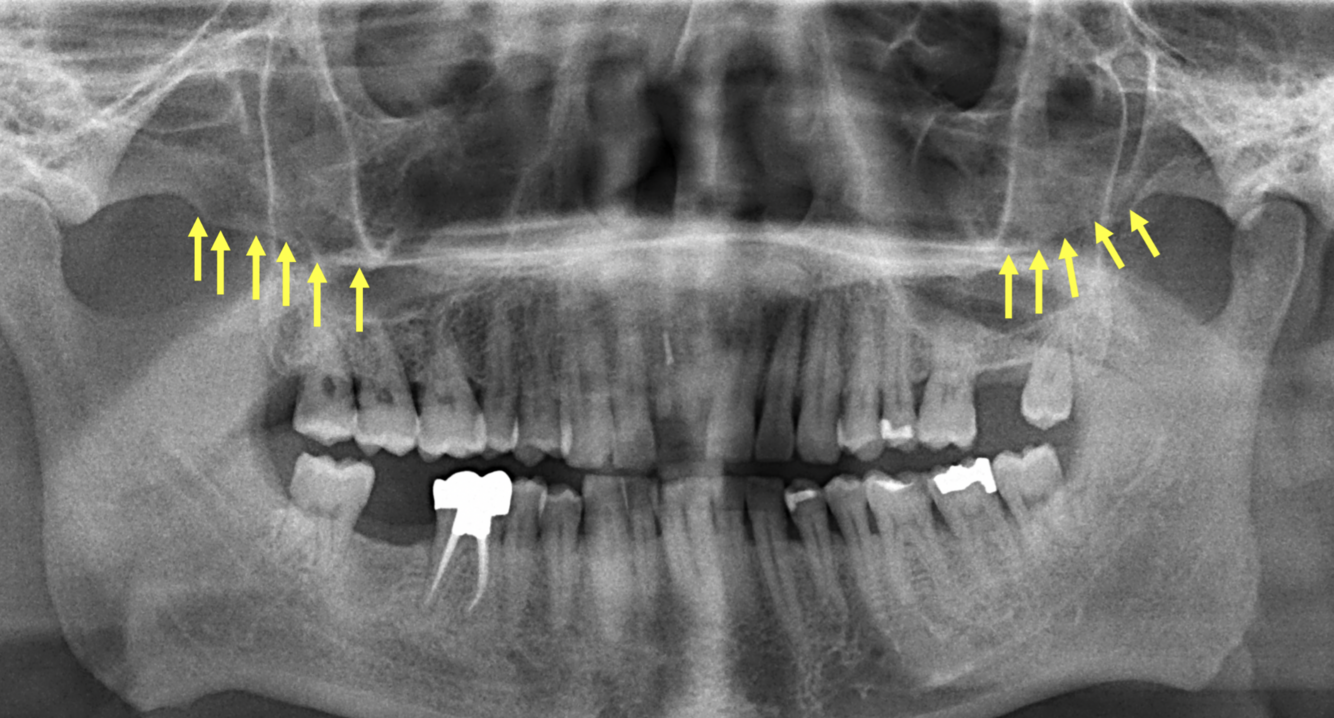

X

74

What do the yellow arrows indicate in the following image?

Ears